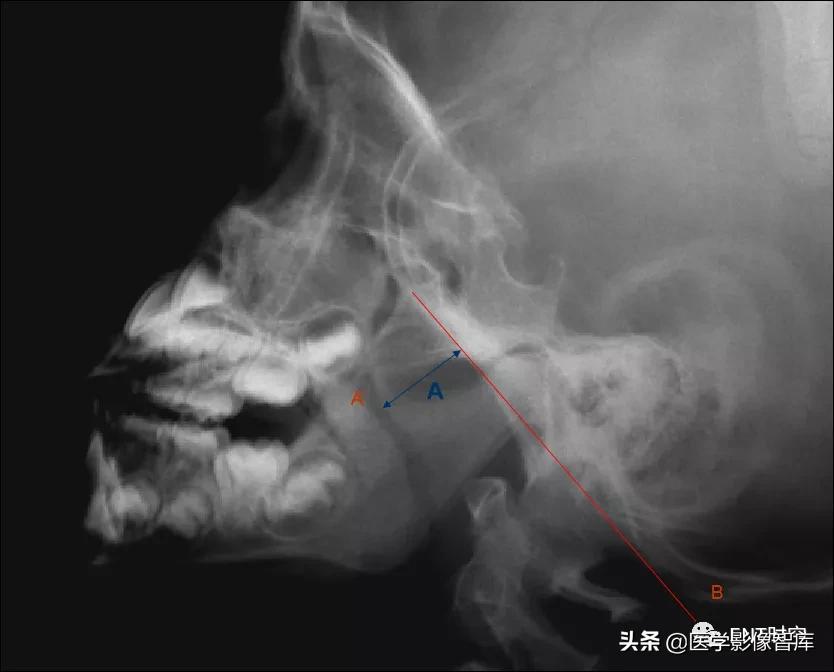

腺样体厚度(A)的测量:

腺样体最突点至枕骨斜坡颅外面的垂直距离

>13mm,就会出现鼻咽腔气道变窄,甚至闭塞。